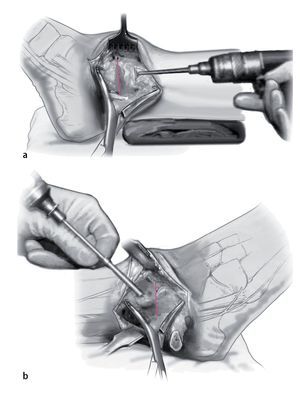

Fig. 1 Incisión lateral (a) y medial (b) . Ambas de 6-8 cm de longitud y el uso del maléolo lateral y medial como puntos de referencia.

Fig. 2 La incisión medial se lleva a cabo hasta el periostio (a). El daño a la vena safena mayor se evita mediante su retracción anterior. En el lado anteromedial, se reseca parcialmente la cápsula anterior (b). El retináculo extensor y los tejidos blandos se pueden mover como una capa para exponer la sección anteromedial de la articulación del tobillo. Se realiza incisión posterior del retináculo sobre el tendón tibial posterior para permitir la colocación protectora de un separador de Hohmann (b). La osteotomía del maléolo medial se realiza con sierra oscilante y se reseca la porción distal (c).

Fig. 3 Aborde el peroné desde un plano lateral en línea recta (a). La cápsula de la articulación se reseca parcialmente para dejar visible la sección tibioastragalina anterolateral (b). Realice una incisión en la vaina de tendón extensor y levante los tejidos blandos de la tibia en una sola capa. Ahora se puede colocar un separador de Hohmann para permitir una mejor visibilidad de toda la sección anterior del tobillo.

Fig. 4 En el ángulo posterolateral se realiza incisión en la vaina tendinosa peronea. Colocar los separadores de Hohmann como protección en posición anterior y posterior del peroné. Realizar osteotomía oblicua del peroné (a) usando la sierra oscilante a unos 6 cm por encima del espacio articular. Se reseca una sección de 8 mm para facilitar la compresión apropiada al final del procedimiento. Gire el peroné en dirección dorsocaudal (b).

Fig. 5 Decortización de la cara medial del peroné distal con sierra oscilante. Esto aumenta la potencia biológica de la refijación.